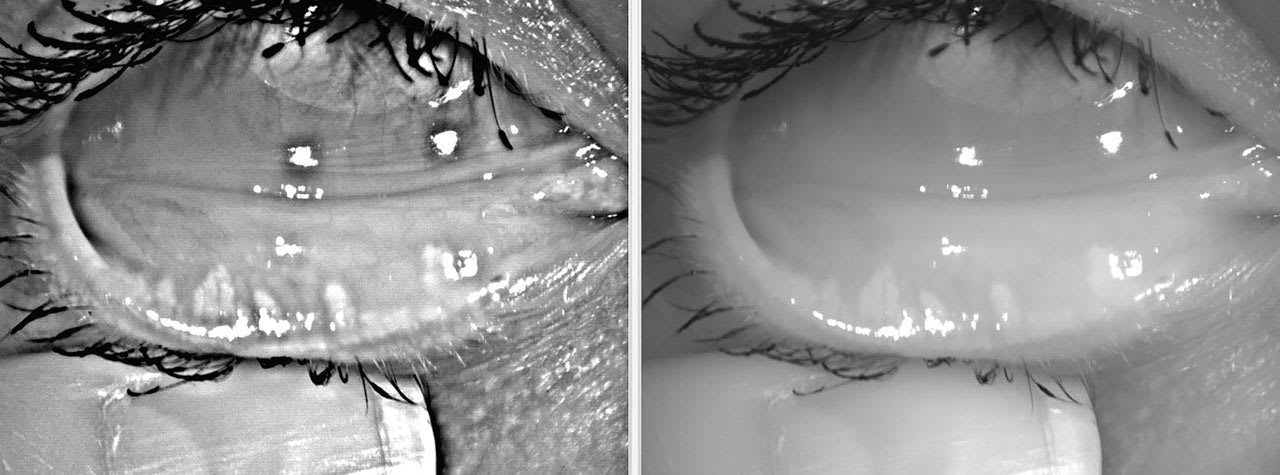

Blepharitis should be aggressively treated with a recommended lid hygiene product (e.g., over-the-counter cleansers, hypochlorous acid sprays, tea tree oil preparations, etc.), topical or oral antibiotics, and Demodex therapies such as topical lotilaner as needed.26 In-office blepharoexfoliation may provide relief by removing microbial biofilm from the lid margins in many cases (Figure 3).27